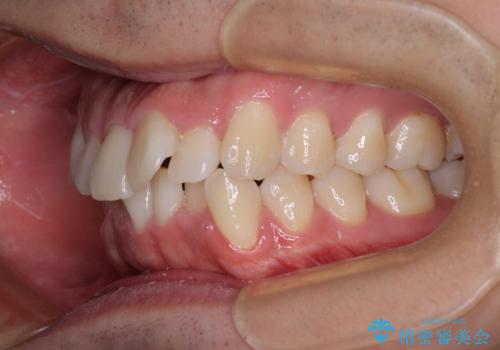

前方に捻れた前歯を治したい インビザライン矯正治療

- 前歯のデコボコを治したいとのことで来院された患者様です。

上下顎ともに歯列全体の後方移動とIPR(歯と歯の間を削る)によってデコボコが解消するように設計し、インビザラインにより治療を行うこととしました。